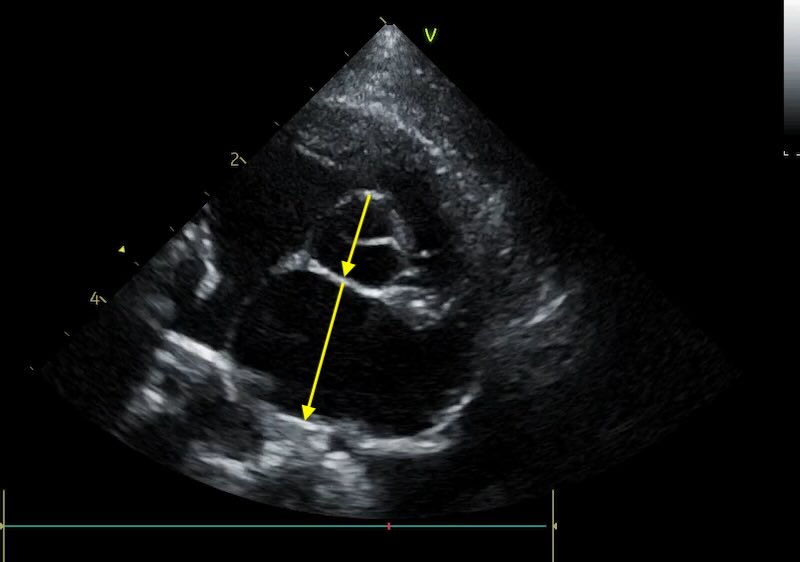

Unlike the LA:Ao, which we time to early diastole, the LAD is measured at end-systole. This is when the left atrium is at its maximal volume, having just finished filling from the pulmonary veins.

- The Timing: Select the frame just before the mitral valve opens (or 1-2 frames after the peak of the T-wave if using an ECG). This is easy with practice, scroll backwards in your loop until you have a closed valve, then step forward frame by frame until it pops open, and go back again 1 frame.

Caliper Placement:

Measure the distance from the inner wall (endocardial border) of the middle of the interatrial septum to the inner wall of the posterior free wall.

The line must be at the widest point of the atrium and must remain parallel to the mitral valve annulus.